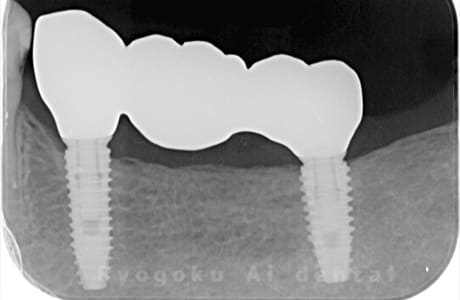

Case09

-

- 原因

- 左下5、6、7欠損

- 治療内容

- インプラント治療

- 治療費用

- 約700,000円

欠損部に歯が欲しいとのことでご来院された患者様です。インプラント治療を行い、現在も経過良好です。

<リスク・副作用>

治療後、痛みや違和感、出血、腫れなどが出る事があります。喫煙者、糖尿病などの方の場合、歯が生着しない場合があります。